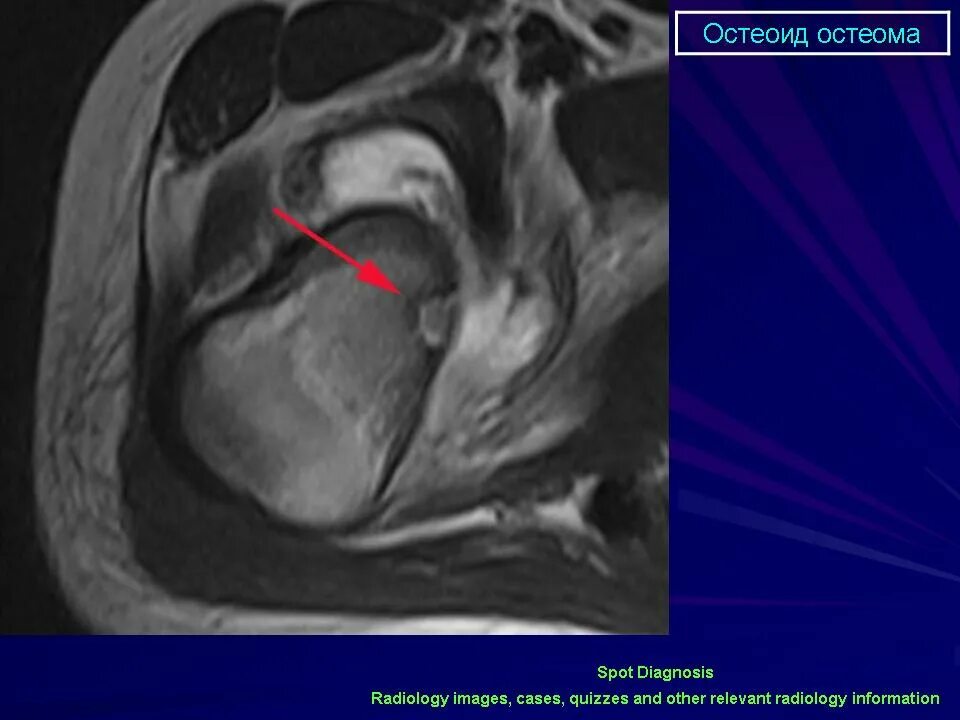

Остеома мрт